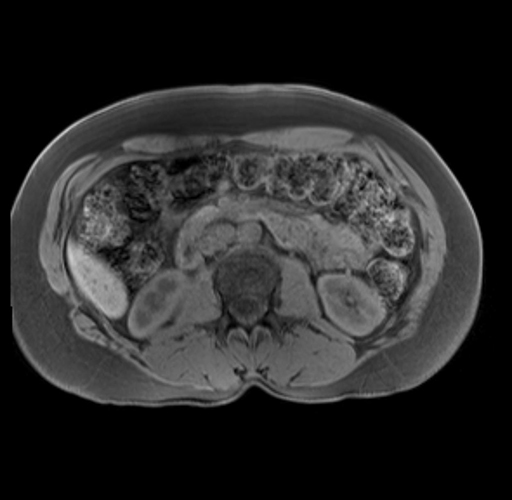

Imaging Analysis

Look through the patient's CT scan to identify any areas of concern for the necessary procedure.

Based on your CT findings, which issue(s) are present and would give reason for "planned slowing down moment(s)" in this case?

Considering a standard distal pancreatectomy procedure, what step(s) of the operation would you do differently in this case?